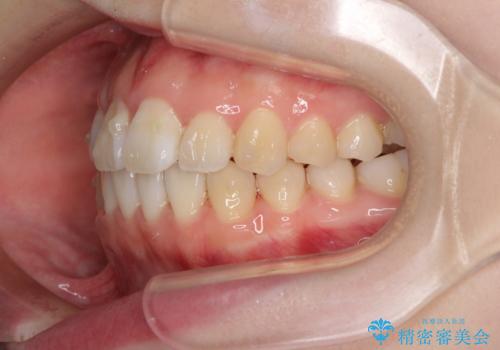

- 前歯の捻れと、ちょっとした出っ張りを気にして来院された患者様です。

歯と歯の間を削る(IPR)ことでデコボコを解消し、インビザラインで整えることとしました。

インビザライン治療特有の奥歯が接触しない時期が続き、当初予定よりも期間がかかりましたが、最終的には安定した咬み合わせと、整った前歯になりました。